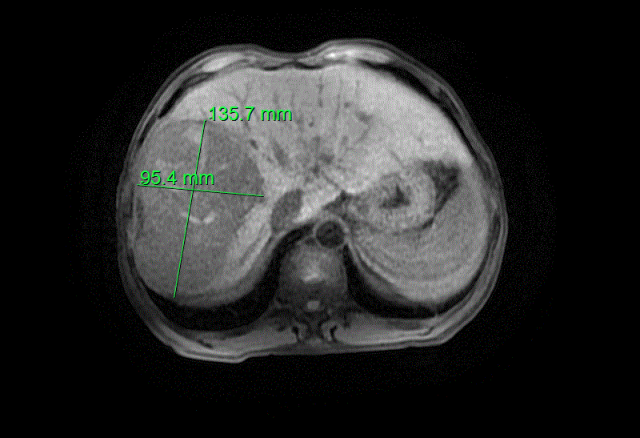

介入治疗前肿瘤大小

面对患者极其复杂的病情,科室第一时间启动多学科会诊机制,迅速集结介入科、肿瘤科、ICU等多领域专家,展开全面深入的会诊讨论。专家团队经过反复细致的研判,一致认为直接实施根治性切除术风险过高,决定先为患者开展转化治疗——即介入治疗联合靶向免疫治疗,力争通过这一方案缩小肿瘤,提升手术可切除性。在多学科团队的精准把控与协同配合下,转化治疗取得显著成效:患者的肿瘤明显缩小,身体状况逐步改善,经术前肝脏三维重建精准测量,其残余肝脏体积占标准肝体积的比例约为60%,已达到手术条件,右半肝切除术的方案就此正式敲定。